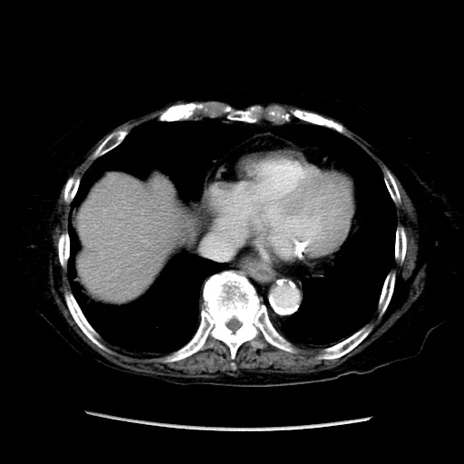

症例14(横断像)

【症例】 90歳代女性

【主訴】 腹痛・嘔吐

【現病歴】今朝から左側腹部痛を認めた。 経過観察していたが、嘔吐を認めたため来院。

【既往歴】 子宮癌術後

【身体所見】 意識清明、BP 127/54mmHg、P 98bpm Sp02 95%(RA)、BT 35.8°C、腹部平坦・軟腸ぜん動音聴取良好、右下腹部圧痛(+) 反跳痛なし

【データ】WBC 9800、CRP 0.46